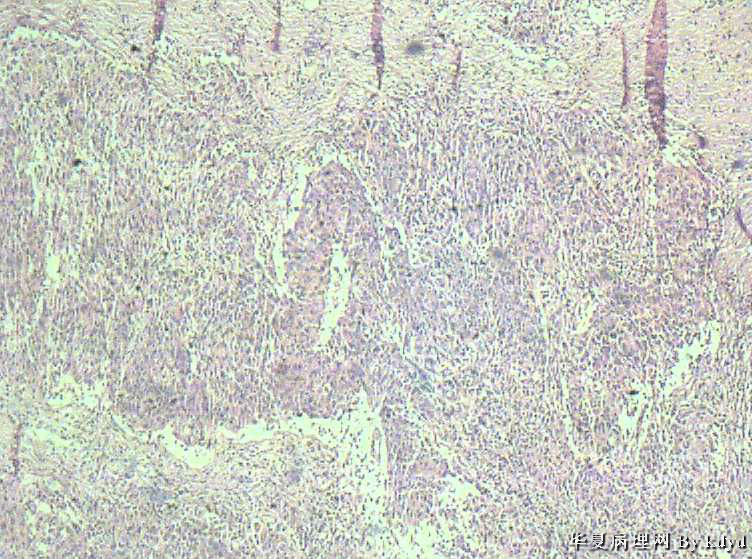

B3997左乳肿瘤--浸润性导管癌?

37岁,女。左侧乳腺肿块发现5个多月,伴隐痛。

手术见:肿块与周围组织分界不清,无明显包膜。

大体:不整形组织大小约3.5*35*2CM,未见明显包膜。质较软,切面浅黄色,一侧见一小囊腔直径约0.8CM囊壁较粗糙。

• 左乳肿瘤--浸润性导管癌?图4

图4

标签:乳腺浸润性导管癌 原位癌

浸润性乳腺导管癌?

IDC

乳腺浸润性导管癌

囊壁内大量炎细胞浸润,囊壁被覆细胞有明显异型,可见核分裂,考虑癌,不知有无陷阱

浸润性导管癌

诊断乳腺浸润性导管癌确实有些担心,制片质量确实要提高,制作优良的切片,是正确诊断的前提。